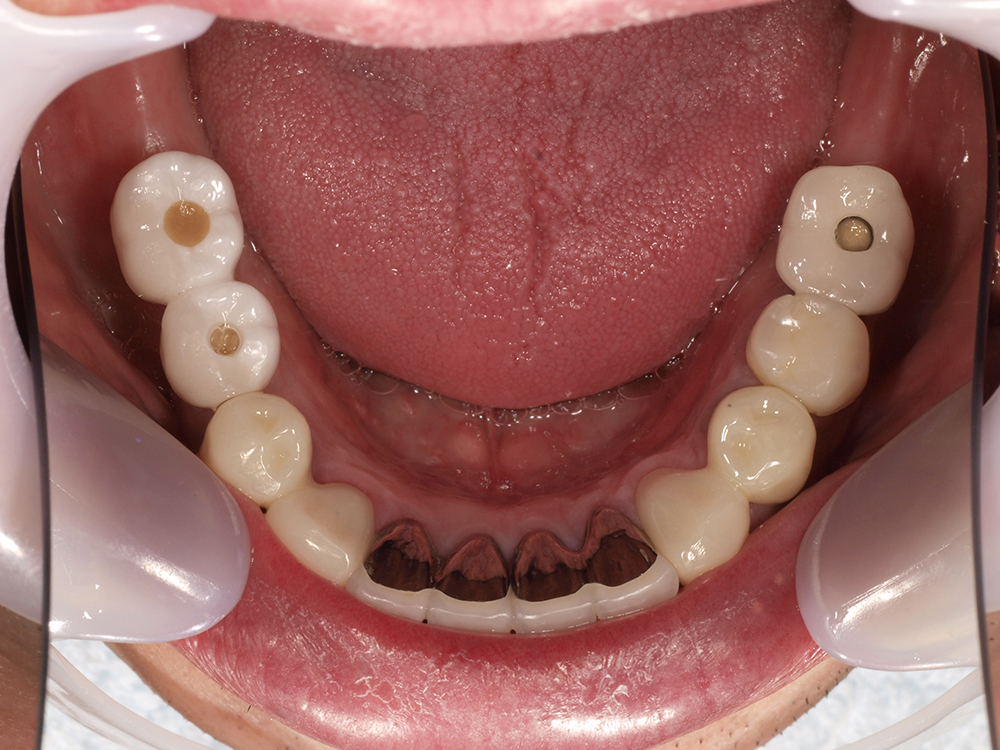

55歳 男性

- 主訴

- 前歯でしか咬めなく、食事を採るのに非常に困難で辛い

- 処置内容

- 上顎6本、下顎3本

- 治療費用

- 上顎:約230万(税込)下顎:約120万(税込)

- 治療期間

- 上顎:1年(仮歯まで8か月)下顎:8か月(仮歯まで5か月)

- リスク

- 上部構造物、仮歯の破折、術後の腫れ(3日)、人工歯根脱落リスクがあります